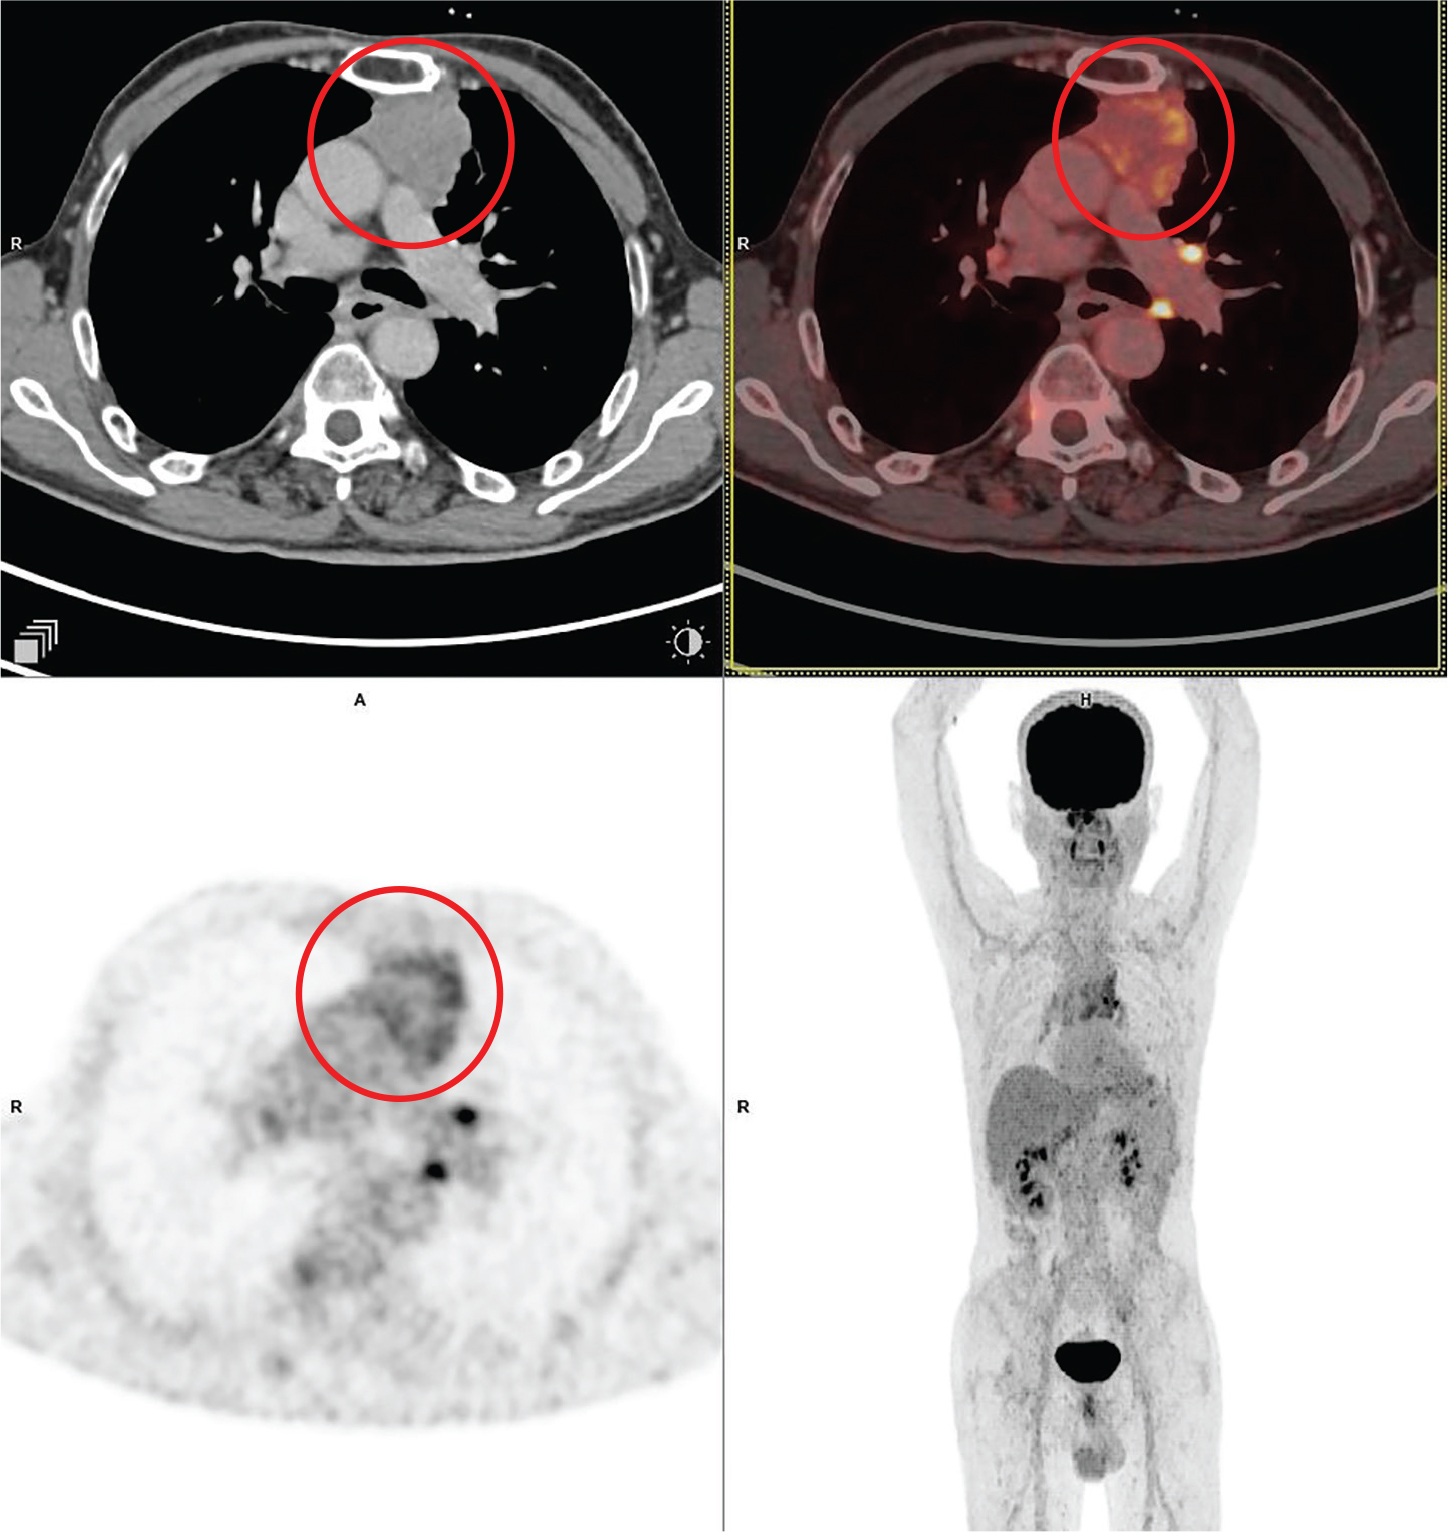

Fig 6

Figure 6. Posterior mediastinal mass that was pathologically confirmed as neuroblastoma. 68Ga - dotatate PET/CT images include axial CT (top left panel), fused axial PET/CT (top right panel), axial PET (bottom left panel), and maximum intensity projection (MIP) PET image (bottom right panel). In the red circle, a large lobulated heterogeneously 68Ga - dotatate avid and enhancing mass is seen involving the left chest cavity and posterior mediastinum with contiguous extension across the midline, and into the superior midline retroperitoneal / posterior abdominal cavity regions. There was additional 68 Ga - dotatate avid mass involving the paranasal sinuses, orbits, nasal cavity, facial bones and multiple other sites of skeletal involvement (not on the included PET/CT images and could be appreciated on the MIP image) that were suggestive of metastatic disease.